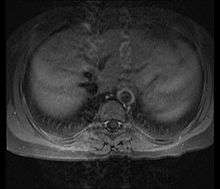

Although the cause of Takayasu arteritis is unknown, the condition is characterized by segmental and patchy granulomatous inflammation of the aorta and its major derivative branches. This inflammation leads to arterial stenosis, thrombosis, and aneurysms.[3] There is irregular fibrosis of the blood vessels due to chronic vasculitis, leading to sometimes massive intimal fibrosis (fibrosis of the inner section of the blood vessels).[5] Prominent narrowing due to inflammation, granuloma, and fibrosis is often seen in arterial studies such as magnetic resonance angiography (MRA), computed tomography angiography (CTA), or arterial angiography (DSA).

Diagnosis is based on the demonstration of vascular lesions in large and middle-sized vessels on angiography, CT, or magnetic resonance angiography.[9]

Contrast angiography has been the gold standard. The earliest detectable lesion is a local narrowing or irregularity of the lumen. This may develop into stenosis and occlusion. The characteristic finding is the presence of "skip lesions," where stenosis or aneurysms alternate with normal vessels. Angiography provides information on vessel anatomy and patency but does not provide information on the degree of inflammation in the wall.[9]